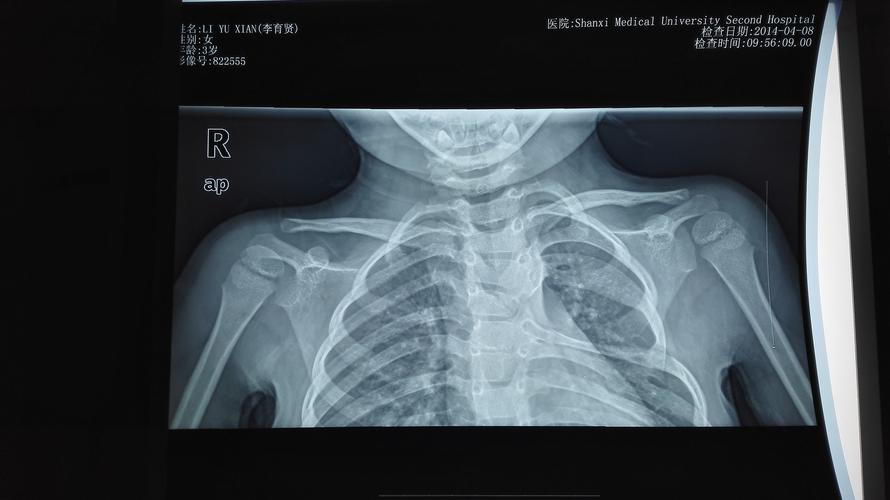

先天性高肩胛术后照片,高肩胛骨症孩子图片

女16岁,合并有先天性高肩胛

高肩胛骨症孩子图片

先天性高肩胛骨症图片